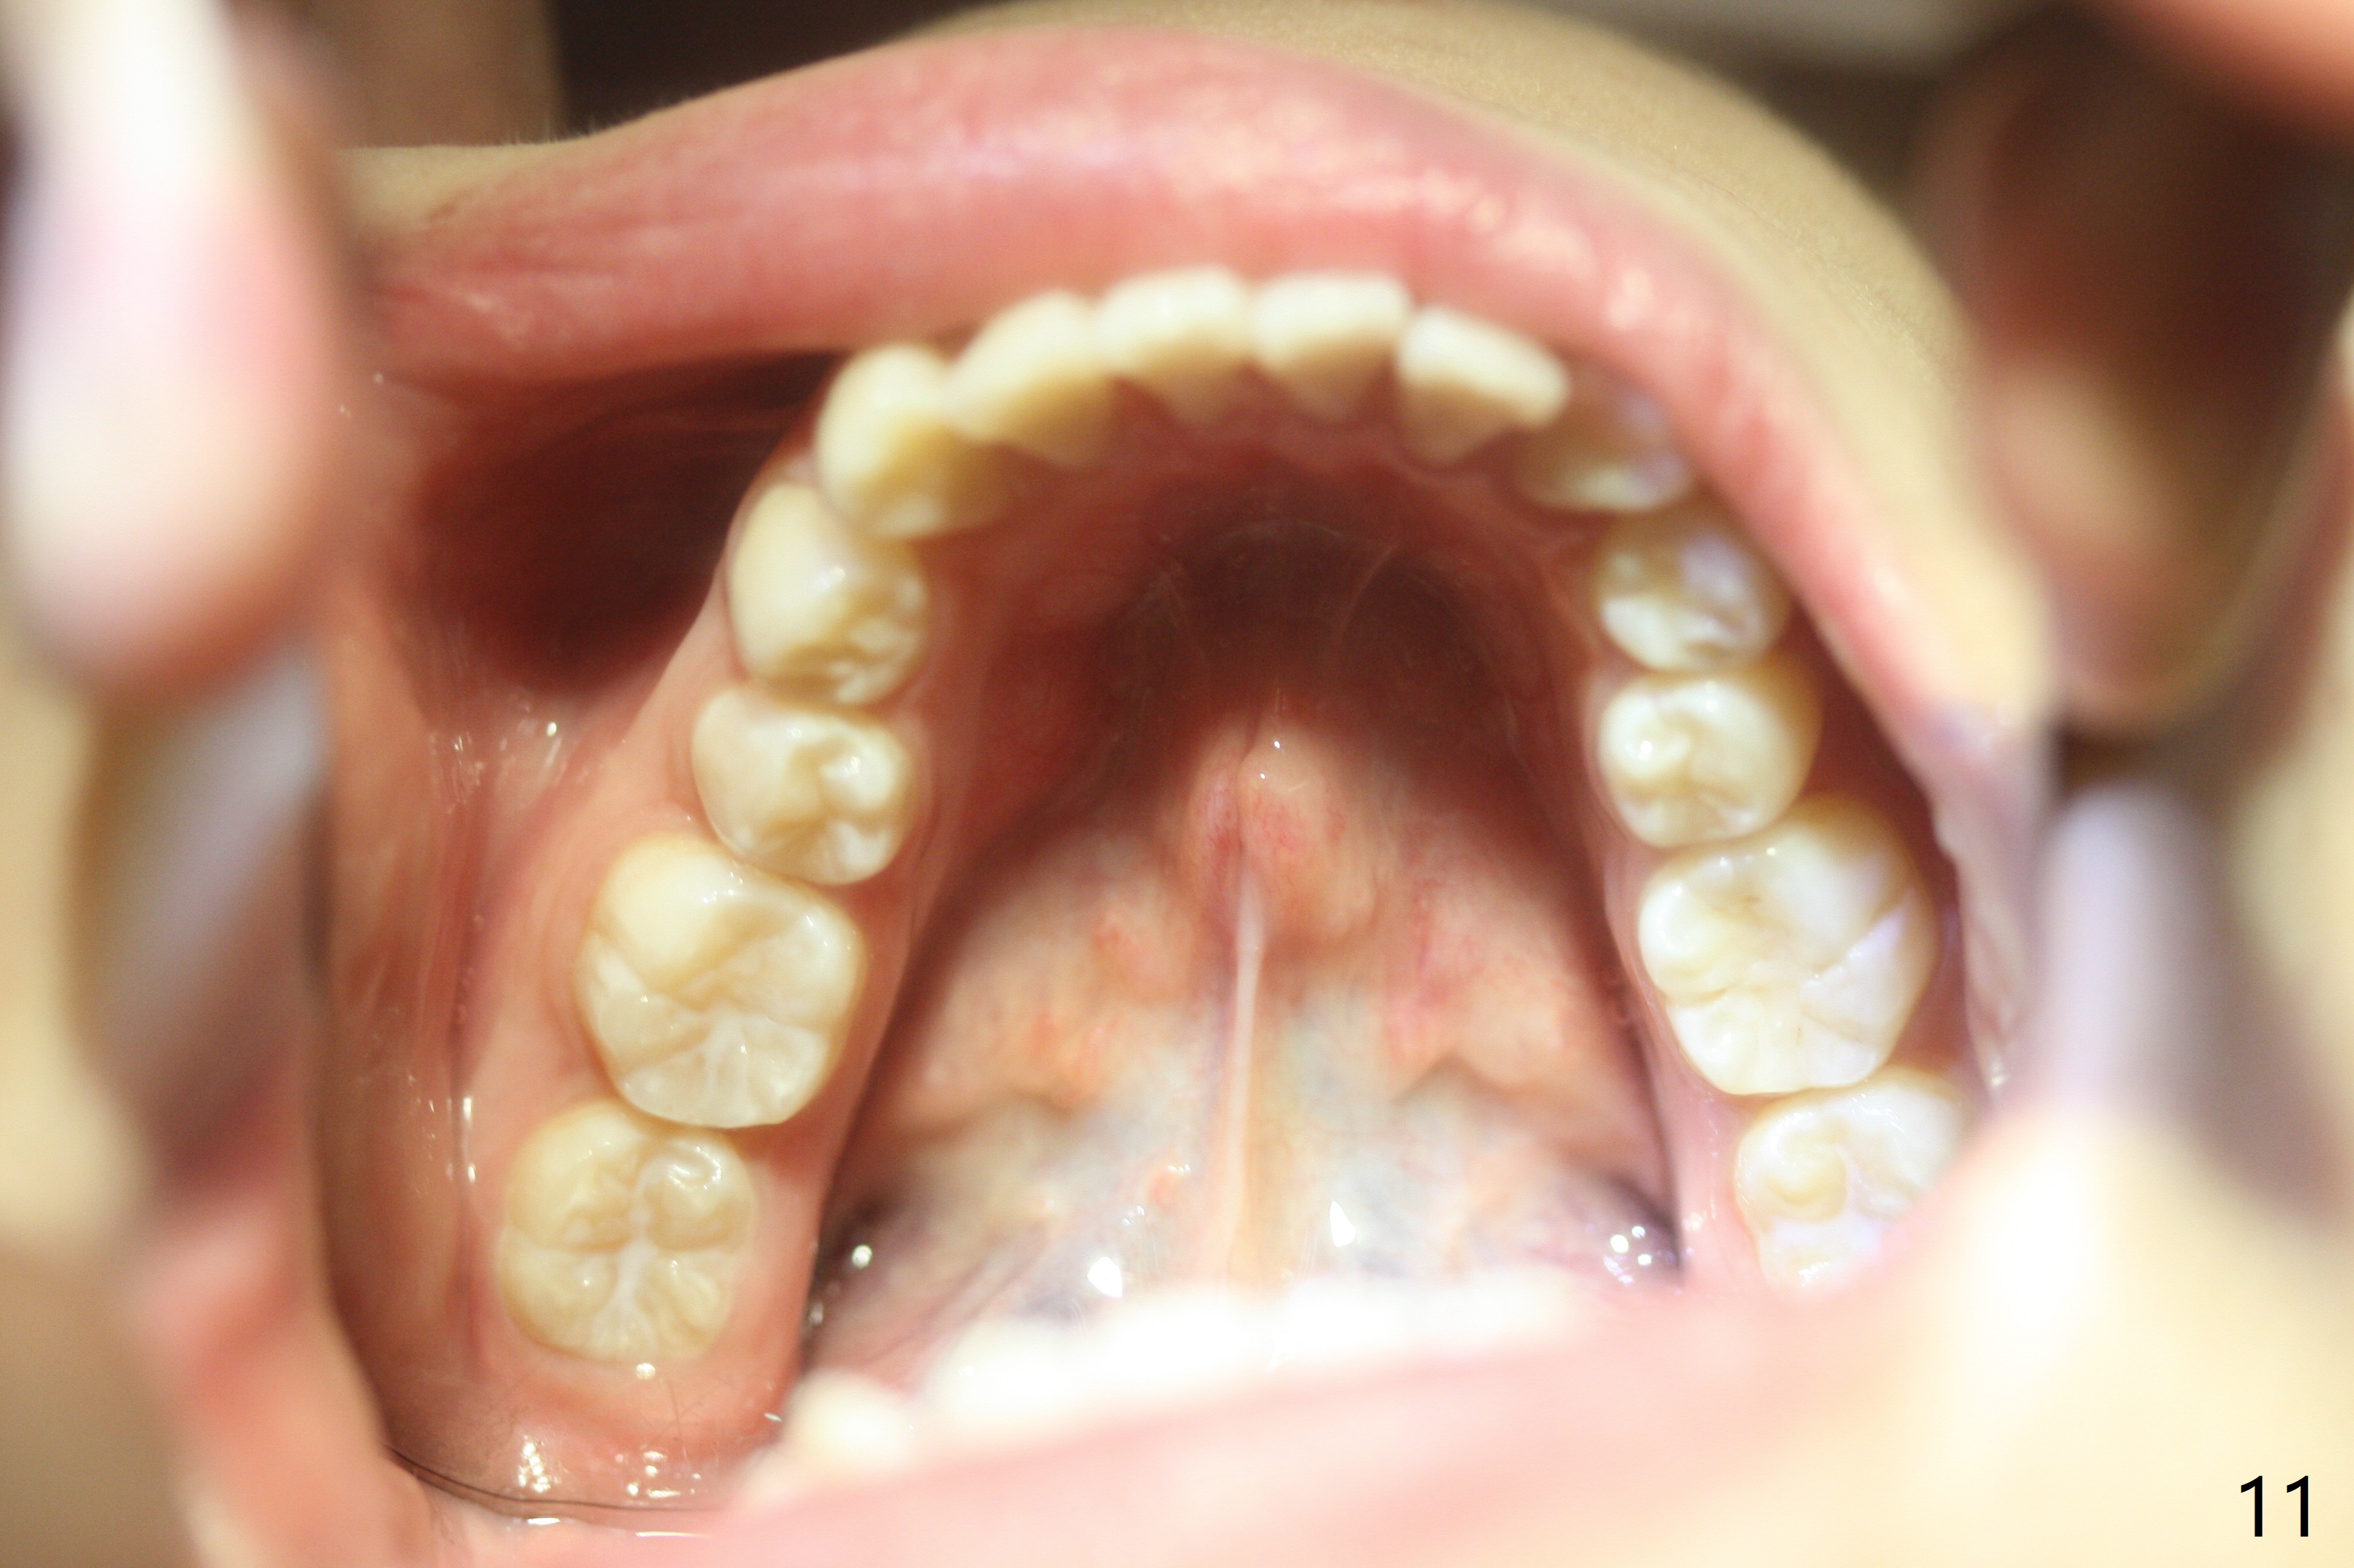

A 15-year-old woman has protrusive lips and retrusive chin (Fig.1-6). Canines and molars have Class I occlusion (Fig.7-9). With 4 bi extraction and 5-7 anchorage (Fig.10-12), 3s will be distalized after 16x16 wires, followed by posted wire retraction of 4 incisors.